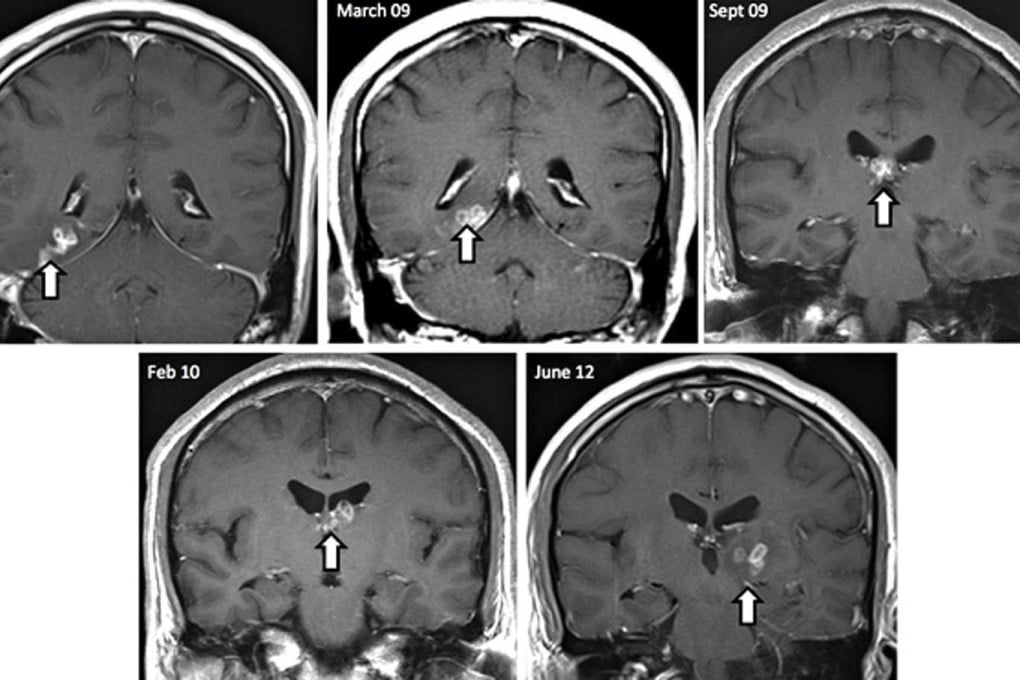

During that time, the parasite travelled from the right side of the brain to the left, absorbing nutrients from the brain itself as it went.

Scientists in Britain have removed and studied a rare tapeworm that lived in a Chinese man's brain for four years, researchers said.